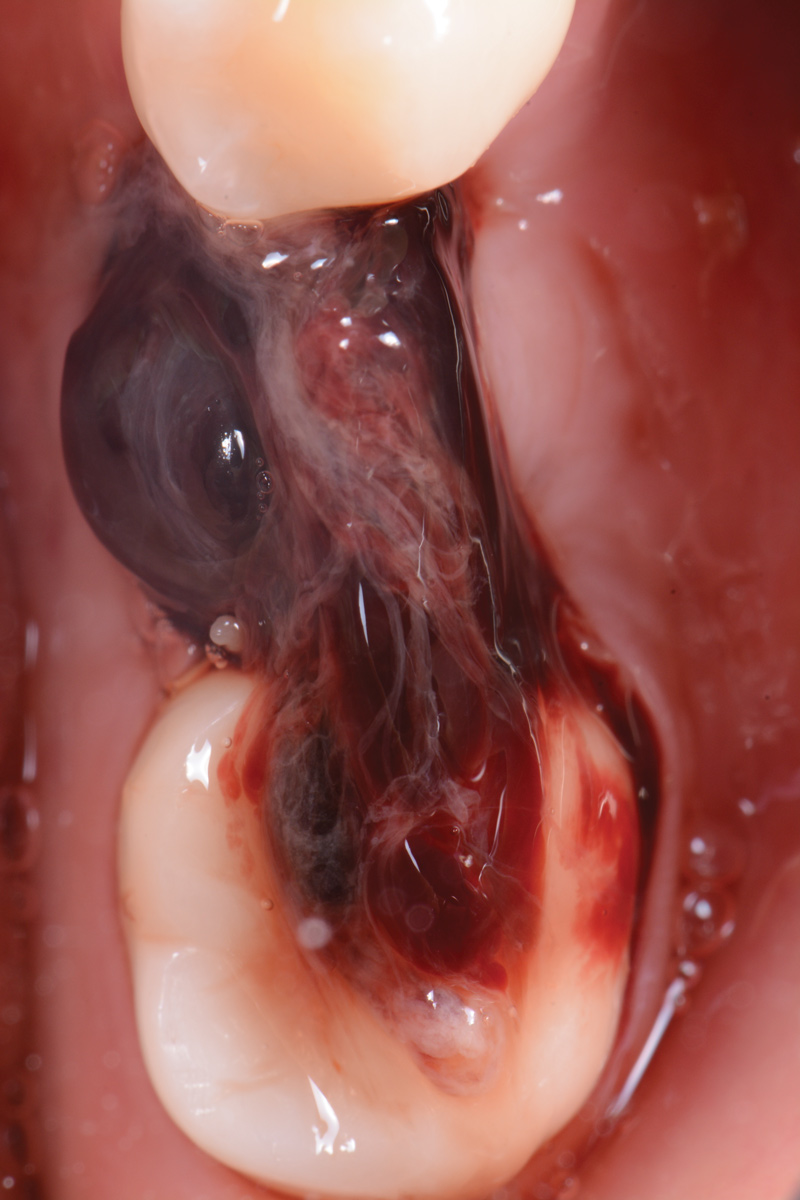

The following day, the patient presented for an emergency, reporting she began to bleed after she left the office and had continuous bleeding that day and night. Vital signs were normal (blood pressure was 115/65 mmHg, and pulse was 53 beats per minute). The first attempt to control the bleeding included having the patient bite on wet collagen wound dressing and alternate using wet- and dry-gauze compression for 30 minutes. After the removal of the collagen wound dressings, the bleeding restarted spontaneously. The sutures were then removed, and a collagen wound dressing was placed under the flap. Two single interrupted sutures were used, and a third suspended suture was placed around the healing abutment to obtain compression in the area. The patient was observed for 1 hour. During this time, wet-gauze compression was used on the area until the bleeding stopped. The patient was then dismissed and told to reapply gauze with pressure if bleeding recurred (Figure 1 through Figure 5).

Fig 3. Wound dressing in place.

Figure 3

Fig 4. Wound dressing secured with two single interrupted sutures and one suspended resorbable suture.

Figure 4